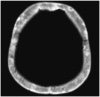

White Cerebellum Sign

On CT imaging, white (or dense) cerebellum sign is seen when the cerebellum appears dense with respect to the cerebral parenchyma. The “increase” in attenuation of cerebellum is in fact a relative hyperdensity caused by decreased attenutation of the brain (Fig. 30). It represents anoxic-ischemic cerebral injury, and has a very poor prognosis (32).

caption a8White cerebellum sign

Another sign associated with severe ischemic damage is the reversal sign, where the gray matter appears hypodense with respect to the white matter, in contrast to the normal appearance where gray matter is denser (57).